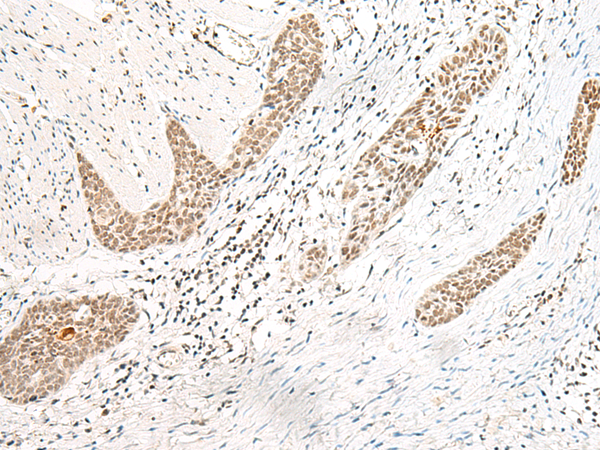

IHC positive control: |

Human esophagus cancer and Human thyroid cancer |